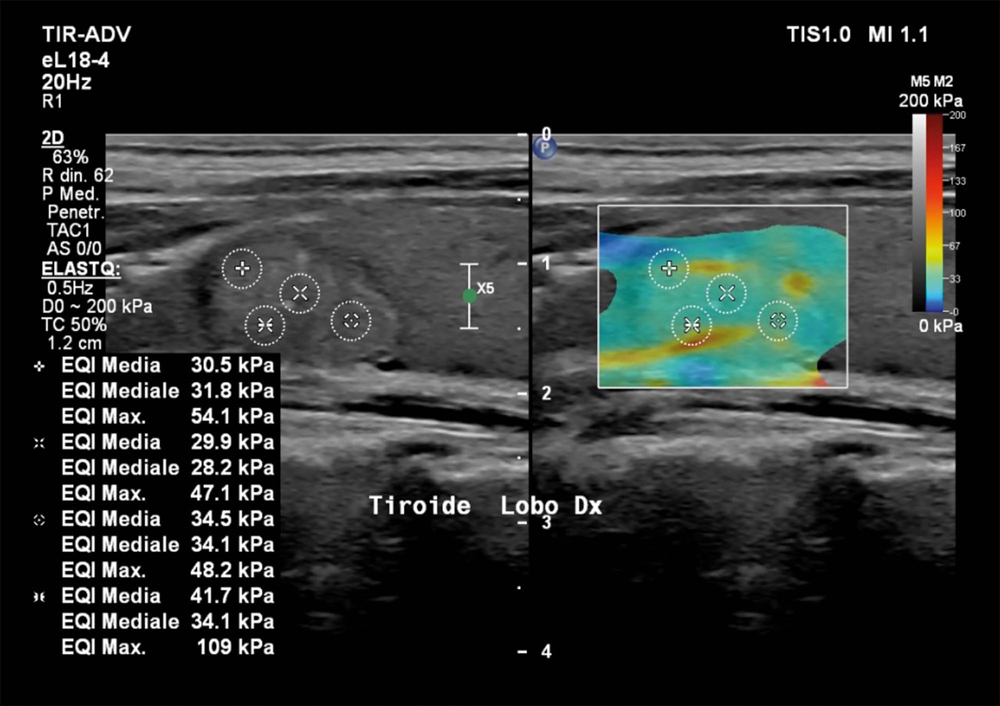

Un altro campo in cui l’elastosonografia ha cambiato la pratica clinica è lo studio dei noduli tiroidei. «I noduli più rigidi possono essere sospetti e meritano approfondimento, mentre quelli più morbidi sono generalmente benigni. Grazie a questa metodica possiamo selezionare i casi che necessitano di un agoaspirato (FNAB) e monitorare nel tempo eventuali cambiamenti». In questo modo l’elastosonografia tiroidea diventa uno strumento prezioso per ridurre biopsie inutili e migliorare l’accuratezza diagnostica. Un supporto prezioso alla diagnosi quindi, non un suo sostituto. L’elastosonografia non sostituisce la diagnosi istologica, ma la integra con un’informazione aggiuntiva e non invasiva. «Il valore reale — sottolinea Ivona — è nel contesto clinico: il risultato va interpretato alla luce della storia del paziente, degli esami di laboratorio e delle immagini ecografiche tradizionali». Il vantaggio è evidente: migliorare la precisione diagnostica, ridurre i rischi e rendere il percorso di cura più personalizzato.